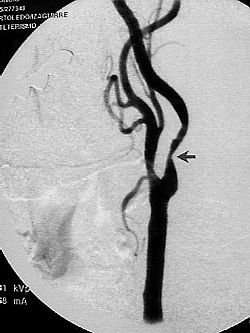

Una manera muy frecuente de la disminucion del flujo es una estenosis (estrechamiento) como se observa en arteriografias inferiores.

Arteriografias tronco carotideo  comun  con sus respectivas ramas int. externa.

Se muestra estenosis A. carotida y posterior angioplastia con recuperacion de espacio luminar.